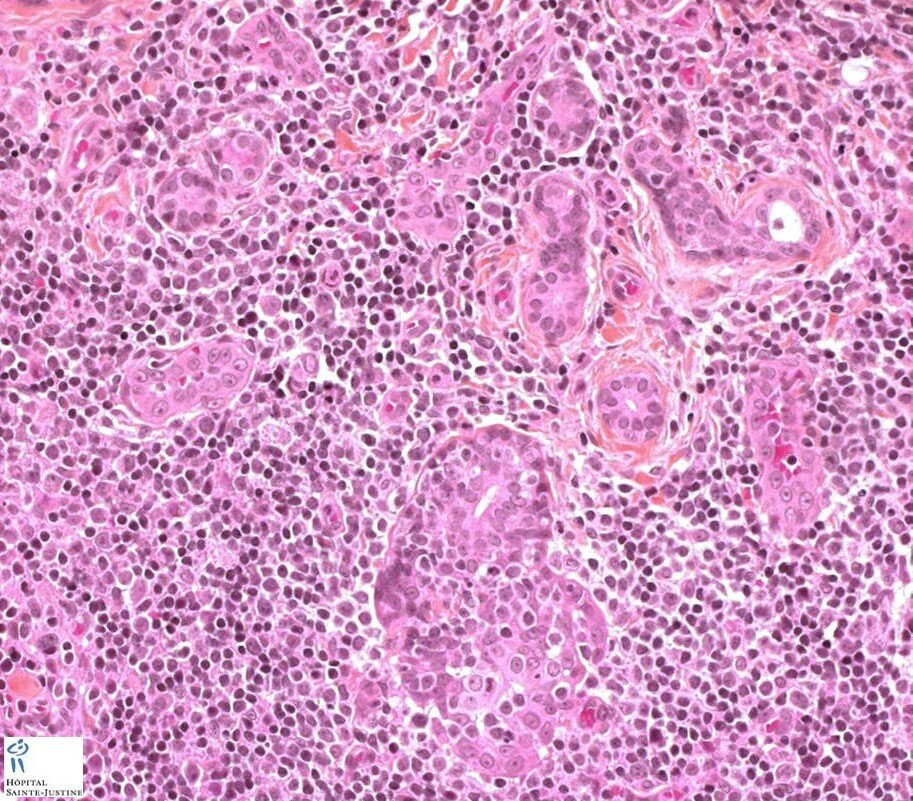

Atypical salivary lymphoid hyperplasia